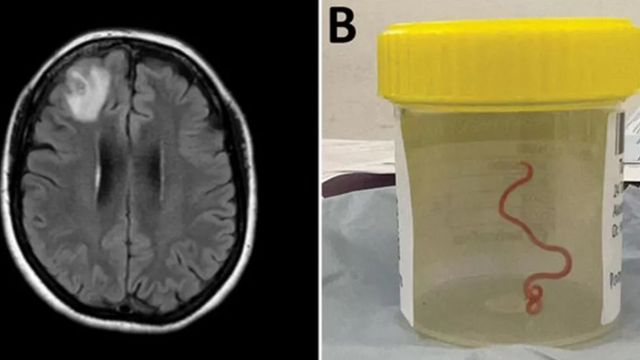

В следующем году женщина начала жаловаться на забывчивость и депрессию. Ее направили в больницу Канберры для МРТ головного мозга, которая выявила «атипичное поражение правой лобной доли головного мозга», требующее хирургического вмешательства.

Во время операции нейрохирург Хари Прия Банди извлекла из мозга пациентки 8-сантиметрового красного червя.

«Канберра - небольшое место, поэтому мы отправили червя, который был еще жив, прямо в лабораторию ученого из CSIRO, который имеет большой опыт работы с паразитами», - сказал Сенанаяке. Тот немедленно определил незваного гостя как Ophidascaris robertsi - круглого червя, часто встречающегося у ковровых питонов, неядовитых змей, обитающих на большей части территории Австралии.